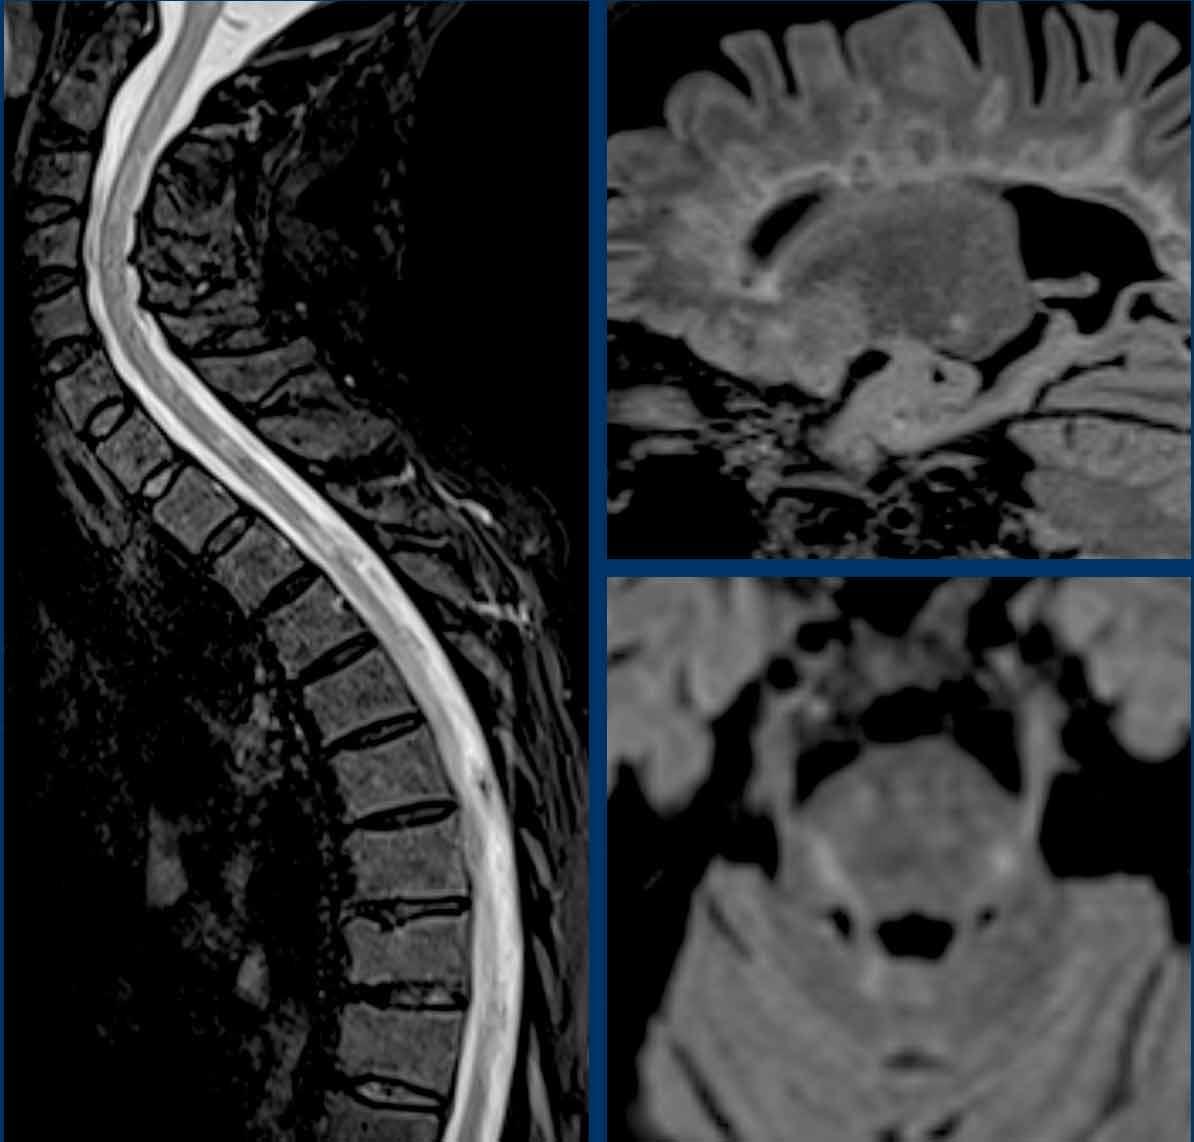

Những hình ảnh này của một người đàn ông 45 tuổi đã bị chấn thương tủy sống do chấn thương ở mức T4-5 vài năm trước.

Hiện tại bệnh nhân có biểu hiện đau tiến triển ở hai chân với giảm phản xạ ở cả hai tay và hai chân cùng với hội chứng Horner hai bên.

Hình ảnh

Hình ảnh cộng hưởng từ cột sống cổ-ngực chuỗi xung T2 TSE theo mặt phẳng đứng dọc năm 2021 cho thấy mất chiều cao thân đốt sống T4 kèm theo tổn thương tủy sống và nhuyễn tủy dạng nang tại vị trí này cùng với hình ảnh rỗng tủy-não thất tủy xung quanh.

Hình ảnh cộng hưởng từ cột sống cổ-ngực chuỗi xung T2W theo mặt phẳng đứng dọc năm 2022 cho thấy hình ảnh rỗng tủy-não thất tủy tiến triển.

Continue with the next images…

Hội chứng Horner có thể được giải thích bởi tình trạng rỗng tủy tiến triển ở mức cổ gây gián đoạn các tế bào thần kinh bậc một của đường dẫn truyền giao cảm nhãn cầu.